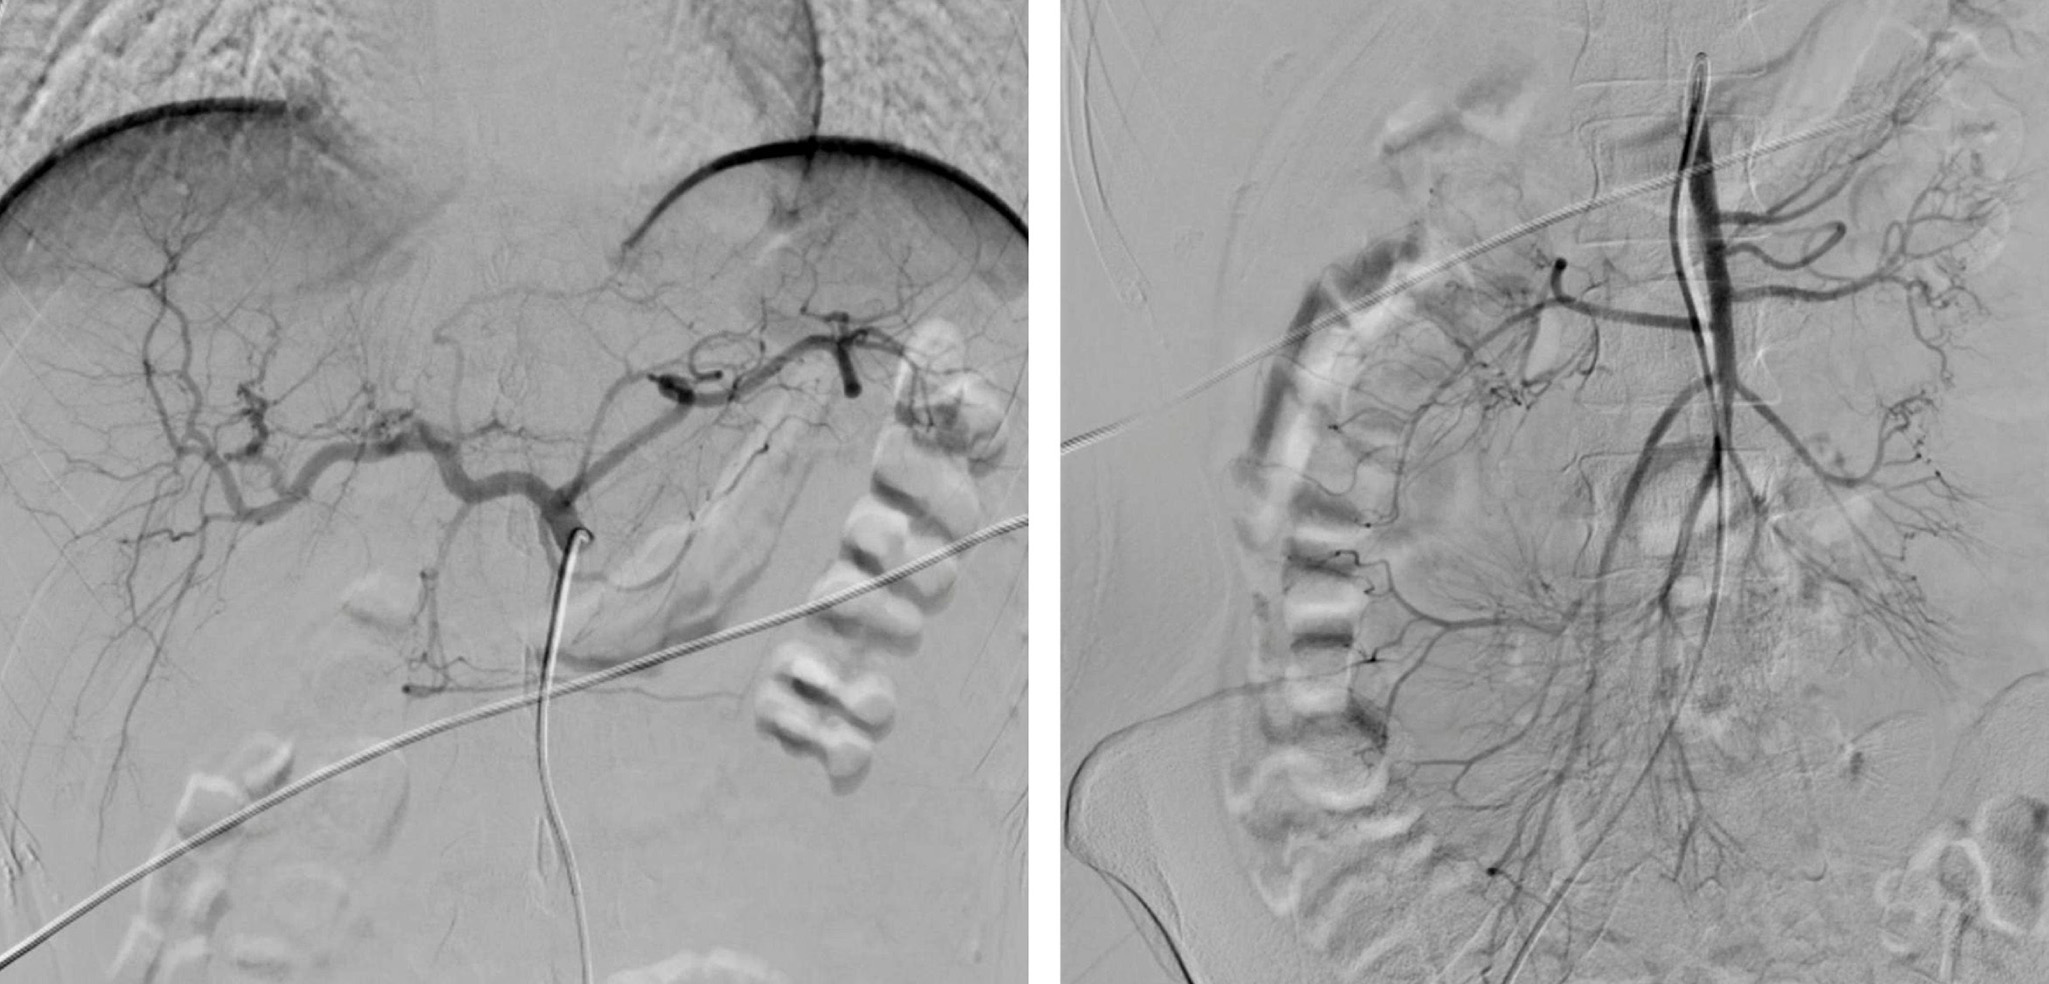

El sangrado del intestino delgado es una causa poco frecuente de sangrado en el tracto gastrointestinal. La mayoría de casos son secundarios a angiodisplasias; sin embargo, rara vez se asocia a hemangiomas del intestino delgado, los cuales son una neoplasia vascular benigna que se diagnostica principalmente con cápsula endoscópica y enteroscopia asistida por balón en pacientes estables de forma preoperatoria. Hasta la fecha solo se había publicado un caso con inestabilidad hemodinámica al momento del diagnóstico. Se reporta el caso de una mujer de 21 años que debuta con sangrado agudo y choque hemorrágico secundario a hemangioma capilar del yeyuno, el cual fue diagnosticado mediante una enteroscopia intraoperatoria y manejado con resección quirúrgica de forma exitosa.